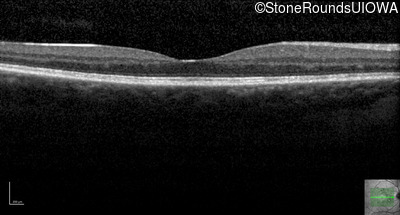

Optical Coherence Tomography - Left - 20/20

Exemplar / OCT Stack

OCT Stack